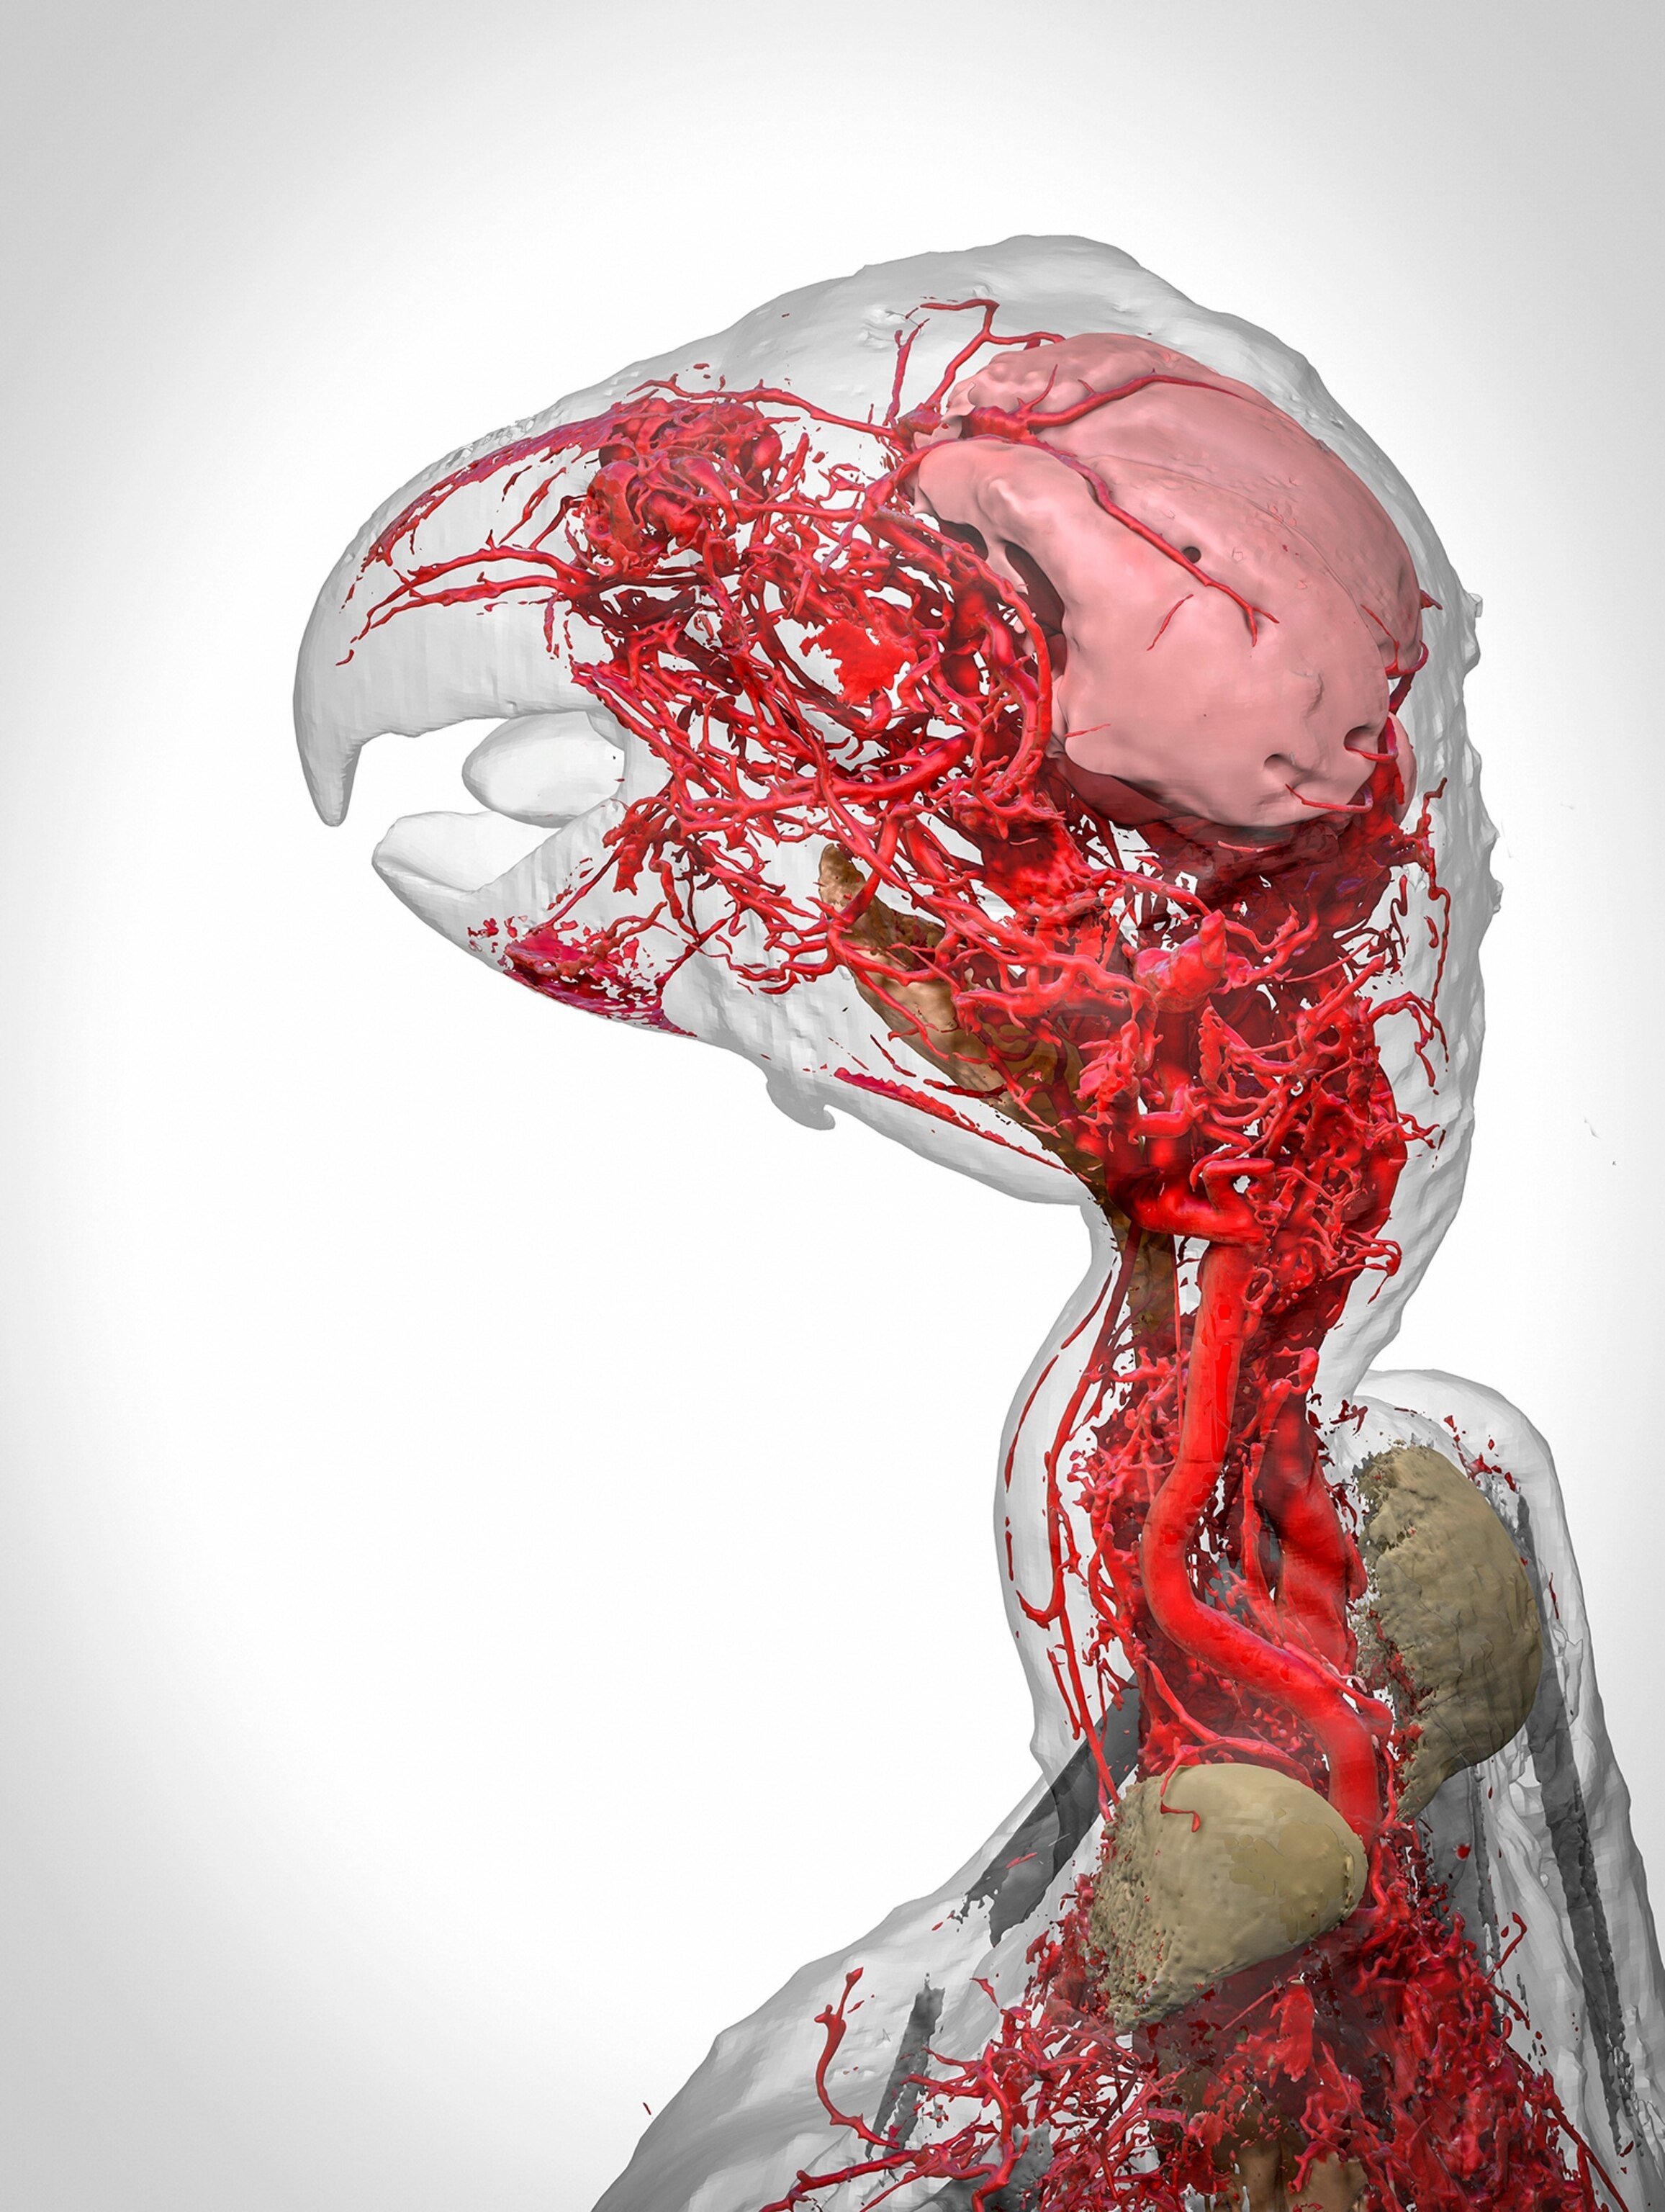

Other notable entries included a digital illustration of Nobel laureate Rita Levi-Montalcini, scans showing intricate blood vessels inside a grey parrot, and a data visualization of how breast cancer is discussed on Twitter.